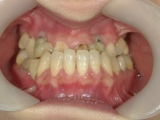

前突が改善し、きれいな歯並びになりました。